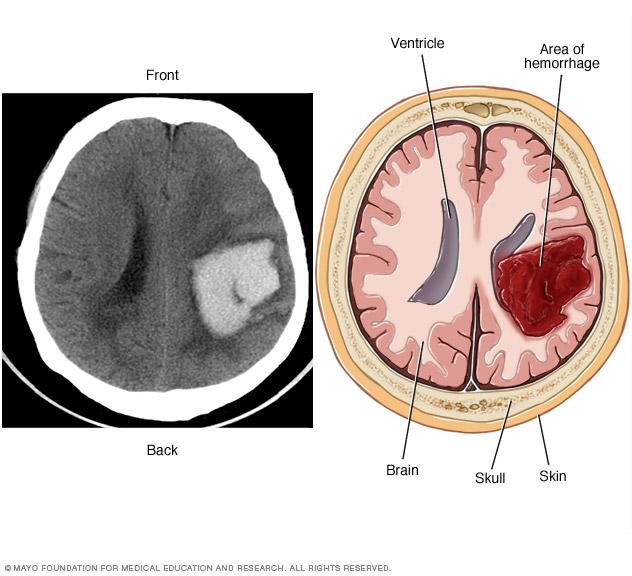

AVM blood flow

In an arteriovenous malformation (AVM), blood passes quickly from the arteries to the veins, disrupting the typical blood flow and depriving the surrounding tissues of oxygen.

Typically, the heart sends oxygen-rich blood to the brain through arteries. The arteries slow blood flow by passing the blood through a series of smaller and smaller blood vessels. The smallest blood vessels are called capillaries. The capillaries slowly deliver oxygen through their thin, porous walls to the surrounding brain tissue.

The oxygen-depleted blood passes into small blood vessels and then into larger veins. The veins return the blood to the heart and lungs to get more oxygen.

The arteries and veins in an AVM lack this supporting network of smaller blood vessels and capillaries. Instead, blood flows quickly and directly from the arteries to the veins. When this happens, surrounding brain tissue doesn't receive the oxygen it needs.